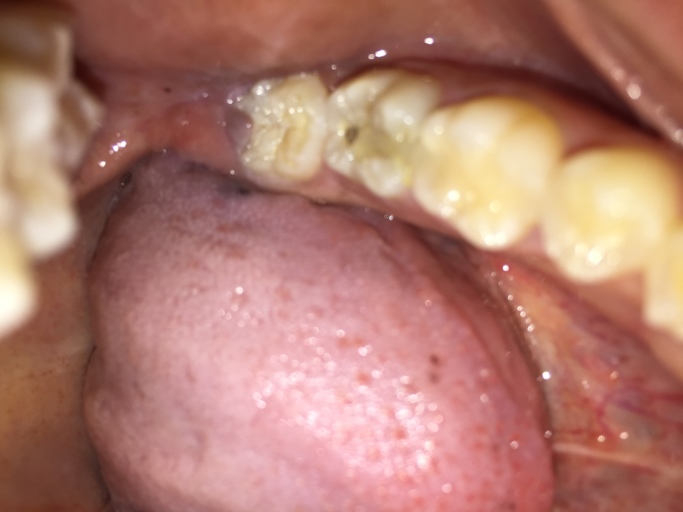

Hi, I am 31 and have observed a dark spot on my lower wisdom tooth (the tooth behind the one with the large silver filling on the picture). All my wisdom teeth have erupted quite good, but short after eruption I had small cavities which were filled...

Is the hole in my tooth a cavity or broken composite filling?

Hello, I have a question about my back molar on the bottom row. I have had white composite fillings as well as sealants in the past years ago. It appears I have a hole in my tooth and it looks as though the filling has broken leaving a nice sized...